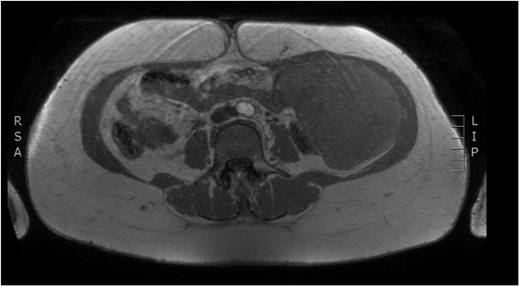

Physical examination revealed a painless, mobile parietal mass on the left anterior abdominal wall, more prominent during cough, of ~13 cm in diameter, with smooth contour and without skin involvement. Laboratory examination including cancer marks showed results within normal limits; hydatid serology (IgG antibodies) was also negative. As ultrasonography results were inconclusive, further imaging with magnetic resonance imaging (MRI) revealed a sizable cystic mass measuring 10 × 13.4 × 11.7 cm, located in the left anterior abdominal quadrant, in the paraumbilical region, between the left internal oblique and the transversus oblique muscle, with projection to the inferior surface of the rectus abdominis. The mass was characterized as a thin-walled cystic lesion, with delayed uptake of intravenous contrast of the wall. High signal intensity was observed on T1-weighted images and low signal intensity on T2-weighted images, with high probability of neoplasia or bleeding (Figs 1–3). No other abdominal or pulmonary lesions were present.

Preoperative MRI. T2 weighted image. Low sign density of the lesion.